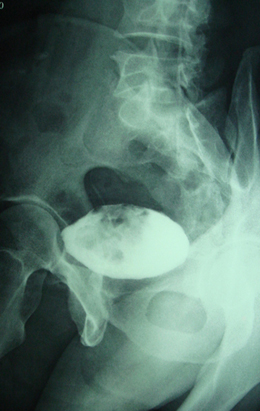

标题: CT28320:典型病例,男,56岁。无痛性血尿3月。 [打印本页]

典型病例,男,56岁。无痛性血尿3月。

膀胱占位性病变,呈菜花状生长,考虑膀胱癌。 期待病理。